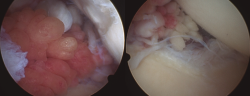

Todos los casos de hombro fueron tratados de manera artroscópica, y los hallazgos incluyeron la presencia de vellosidades características del LA (Figura 3), así como roturas en el seno del manguito rotador. Esta sinovitis proliferativa de aspecto graso se ubicaba predominantemente en la zona del intervalo rotador y en la periferia de la glena e inserción del tendón de la porción larga del bíceps.

Figura 3. Imágenes artroscópicas de las vellosidades del LA en el hombro, así como los cambios artrósicos en la articulación glenohumeral.

En los casos de la rodilla, con una intervención abierta (en el contexto de la colocación de una prótesis total de rodilla) y otra artroscópica, su localización fue predominantemente suprapatelar, si bien también se encontraron vellosidades (Figura 4).

Figura 4. Imágenes artroscópicas del LA en la rodilla, con presencia de vellosidades grasas en el receso suprapatelar e incluso en la zona supra- e inframeniscal.